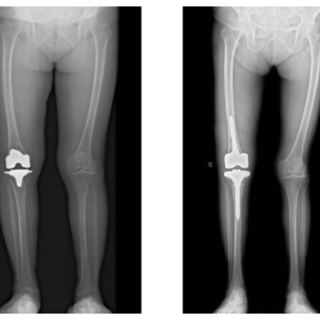

膝关节感染一期翻修:精准诊疗让老人重获行走自由

蒋阿姨右膝关节置换术后3年多,3个月前突发发热,随后出现膝关节疼痛、活动受限,辗转多地保守治疗均无明显效果,最终慕名前往郴州市第一人民医院关节外科就诊。

入院后,科室迅速为其完善检查,标本送检确诊为“甲氧西林敏感金黄色葡萄球菌(MSSA)”感染。依托成熟的感染翻修诊疗体系,科主任赵昀主任医师带领团队,联合麻醉科、手术室、药学部开展多学科协作,制定个性化手术方案,顺利实施“右膝关节感染一期翻修术”。

术后,医护团队给予规范抗感染治疗与个性化康复指导,蒋阿姨的炎症指标逐步降至正常,疼痛症状完全消失,膝关节功能稳步恢复,最终顺利出院,重返正常生活。